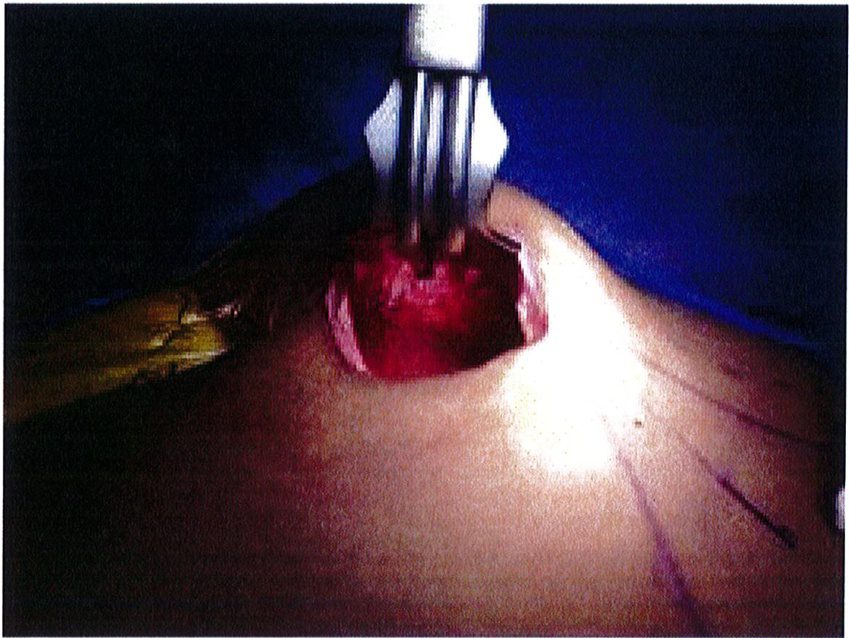

Dụng cụ bóc tách hai đầu tù, hình tròn được sử dụng để phân tách mặt phẳng vô mạch đã được bộc lộ bằng cách tiêm dung dịch trước đó, nhằm bảo tồn tối đa vách và lớp cân mạc. Nên thực hiện bóc tách từ trong ra ngoài, từ trên xuống dưới với một dụng cụ banh có đèn sợi quang (Hình 10). Để tách các vách ngăn, sử dụng một cây bóc tách dài có một đầu nhọn hoặc kéo dài (Hình 11). Các nhánh động mạch mông trên, mông dưới và một số mạch nuôi cho vùng cân mạc được đốt điện. Hãy chắc chắn

Hình. 9. Đánh dấu các mốc giải phẫu quan trọng. (A) Đường rạch cân cơ mông lớn bắt đầu từ bờ ngoài xương cùng (B) Bắt đầu bóc tách lớp cân từ đường rạch ban đầu (Trích từ de la Pena JA, Rubio OV, Cano JP, et al. Subfascial Gluteal aug- mentation. Clin Plast Surg 2006;33:411; đã xin phép trước khi đăng tải.)

Extent of area undermined